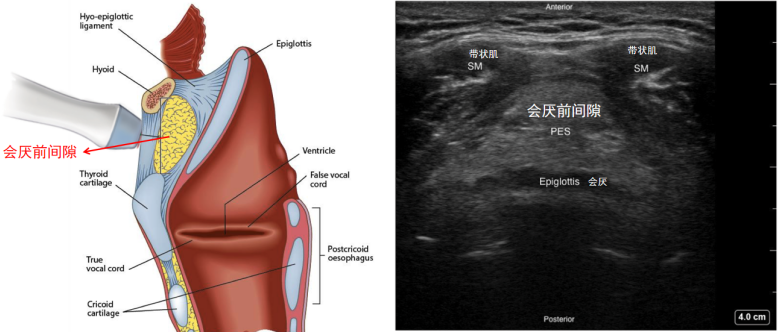

(1)会厌切面:将探头由舌骨向下滑,在到达甲状软骨之前会先到达甲状舌骨膜,在甲状舌骨膜下我们会看到会厌,超声表现为一个线性低回声结构。在会厌切面,我们可以测量会厌到皮肤下的厚度,即会厌前间隙;还可以测量会厌到皮肤的厚度,即会咽深度(图8)。此处越厚,我们在为患者插管时,将会厌提起来越困难,声门暴露越困难,所以会厌前间隙或会厌深度是预测困难气道的重要指标。

图片

图8  会厌切面